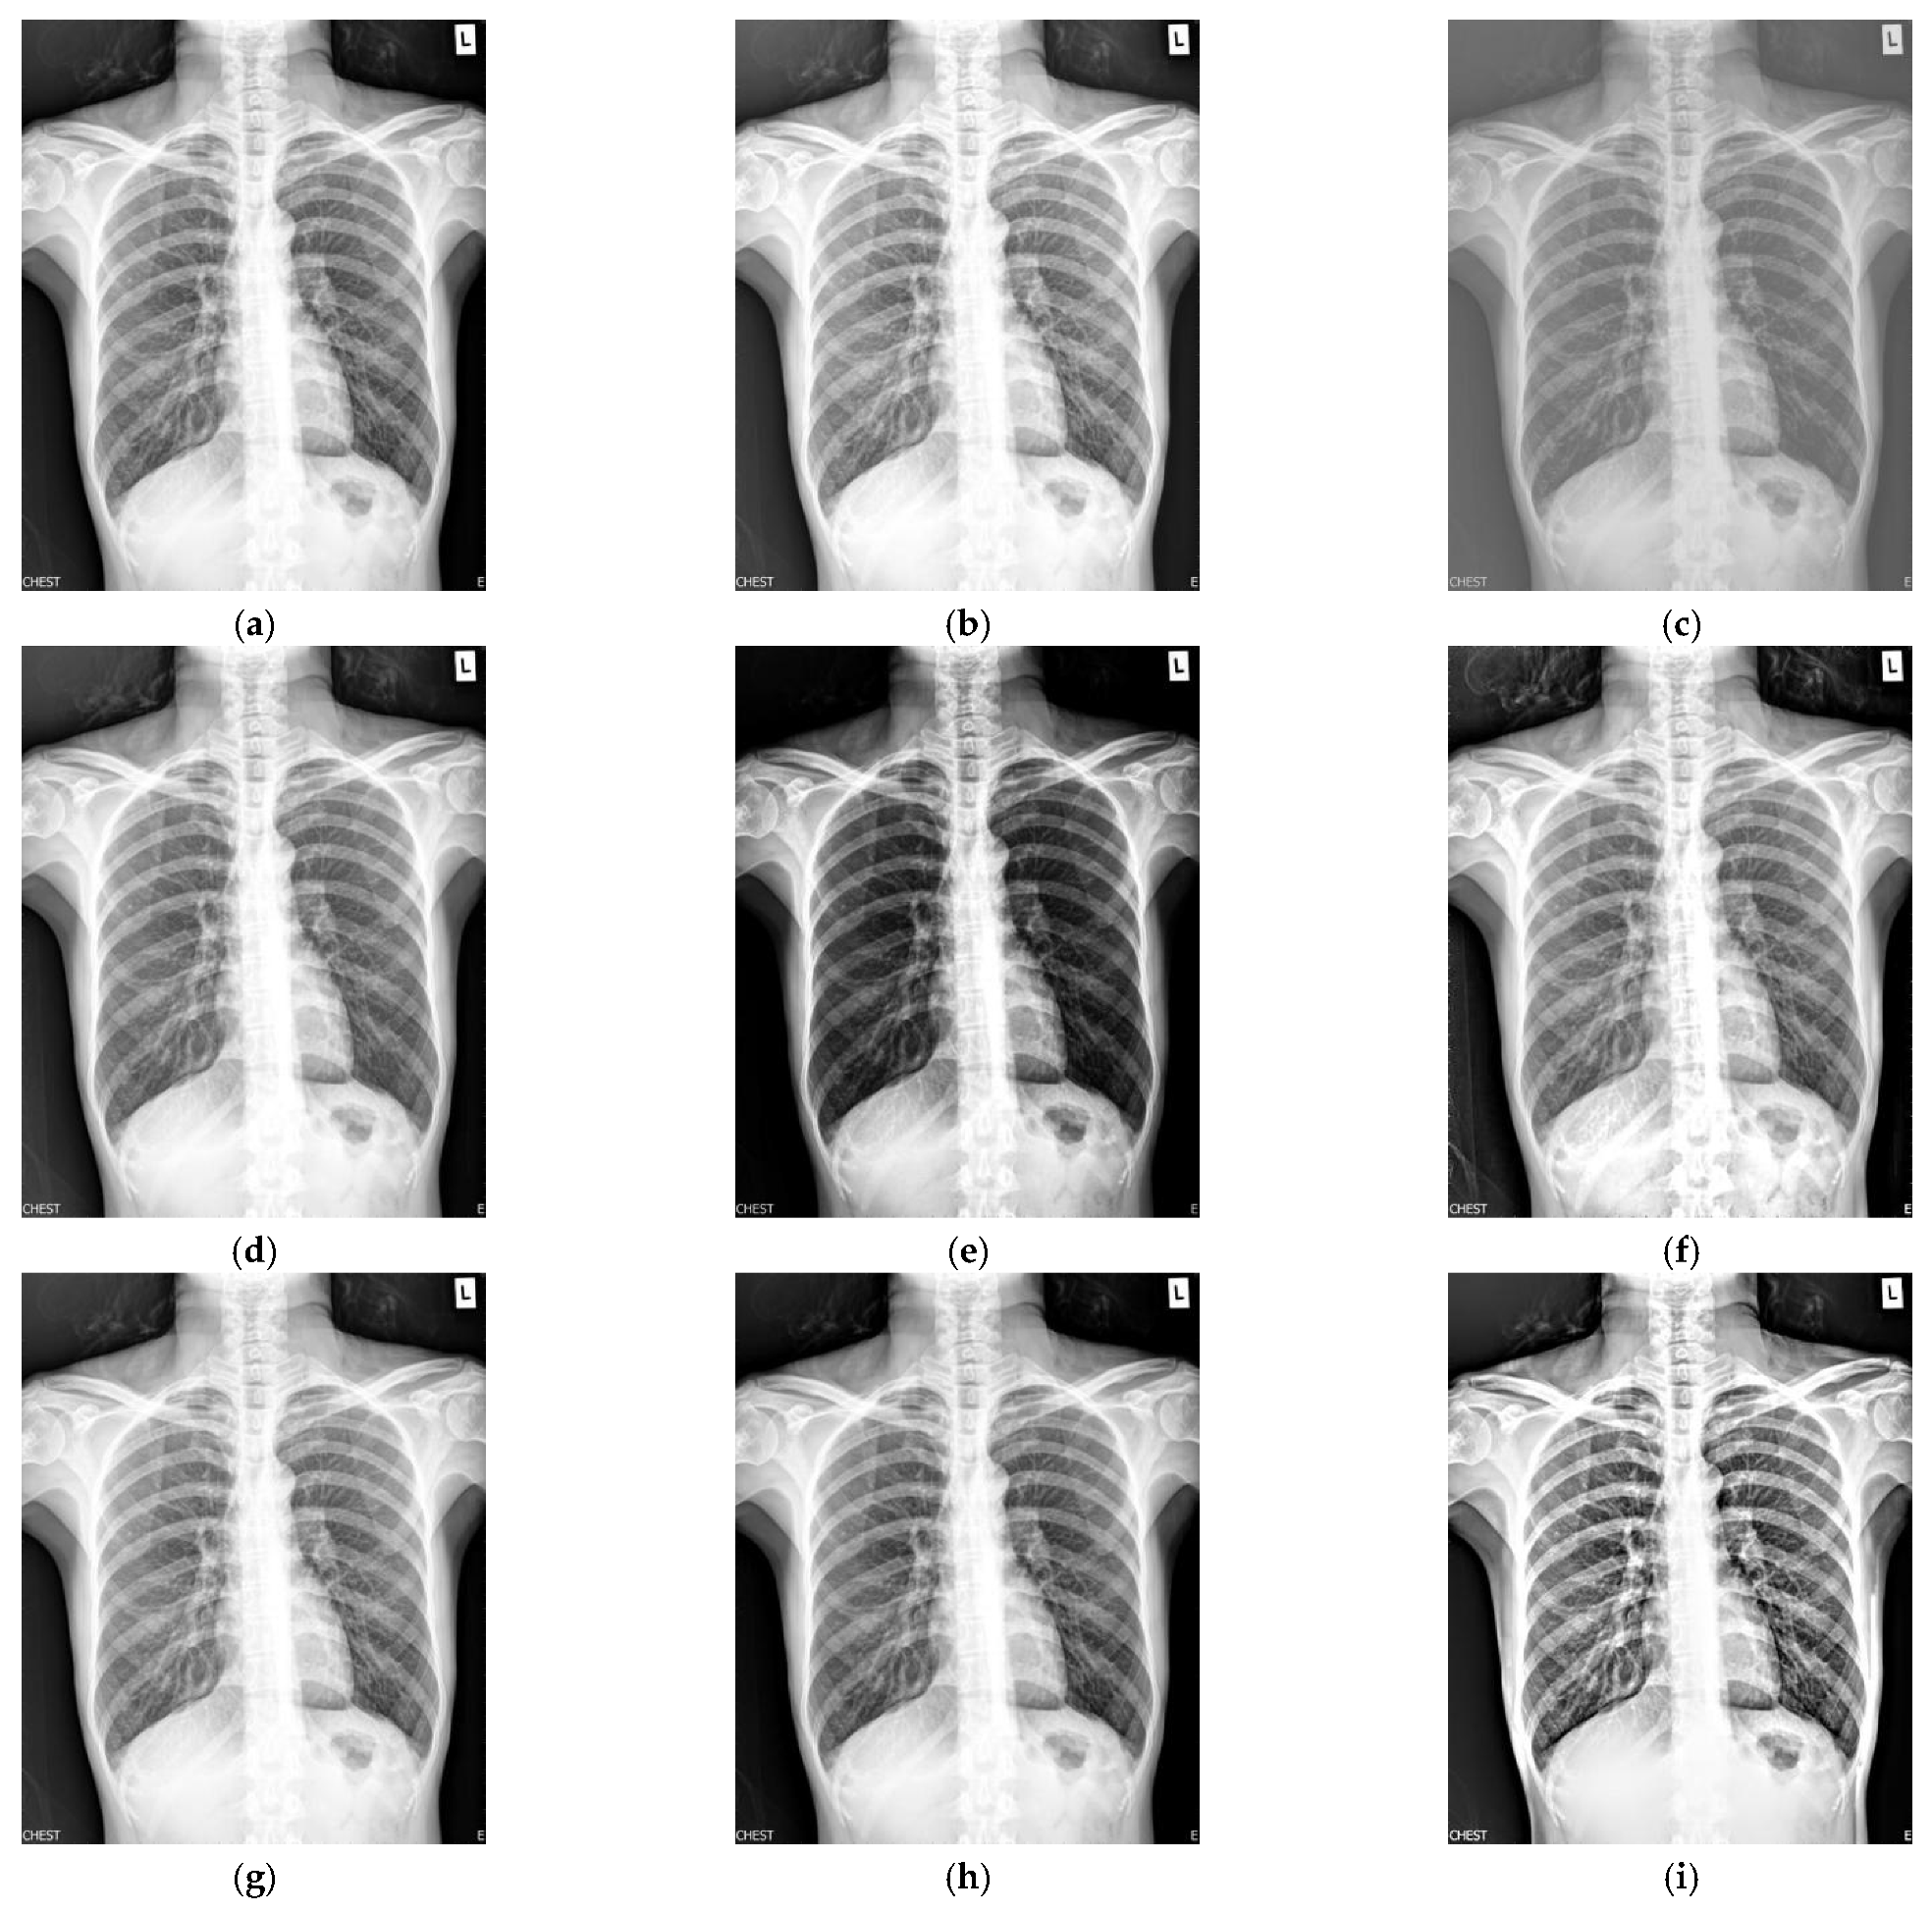

(a) Original Image, (b) Salt and Pepper Noisy Image, (c) Gaussian Noisy X Ray Image Noise Image noise, another component that affects image quality, gives images a grainy appearance and causes random variations of image brightness. The higher the signal and lower the noise, the better the image. The signal to noise ratio (snr) is a measure of the image signal in a given region to the background. In this article we will cover the basics. X Ray Image Noise.